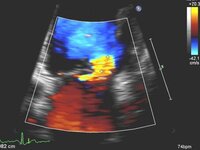

Corte apical de 4 câmaras de regurgitação mitral 4+ (grave) e uma grande área de superfície de isovelocidade proximal

Do acervo de Samir Kapadia e Mehdi H. Shishehbor

Corte apical de 4 câmaras de regurgitação mitral (RM) grave com uma área da superfície de isovelocidade proximal